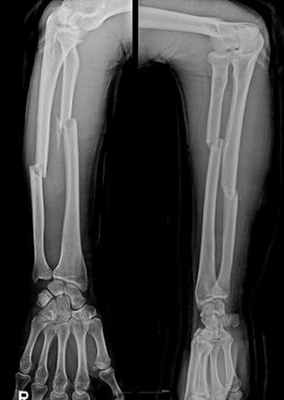

Перелом обеих костей предплечья • Частота — 53% всех переломов костей верхней конечности • Причина: прямая и непрямая травмы • Патоморфология. Характерно сближение отломков лучевой и локтевой кости из-за сокращения межкостной мембраны • Клиническая картина. Больной фиксирует повреждённую руку здоровой рукой. Характерна деформация и укорочение конечности, резкая болезненность при пальпации, осевой нагрузке, сжатии предплечья на удалении от перелома, патологическая подвижность • Лечение •• При переломах без смещения — лонгетно-циркулярная гипсовая повязка в среднем положении предплечья между супинацией и пронацией, тыльном сгибании кисти под углом 25–35° до 8 нед •• При переломах со смещением — одномоментная репозиция ручным способом или с помощью дистракционного аппарата, фиксация гипсовой повязкой на 8–10 нед, чрескостный компрессионно-дистракционный остеосинтез •• При переломах в верхней трети руку иммобилизируют в положении максимальной супинации, в средней трети — в положении полупронации, в нижней трети — вправление в положении пронации, затем переводят в положение полупронации •• Оперативное лечение (остеосинтез) показано при интерпозиции мягких тканей, смещении отломков более чем на половину диаметра, вторичном и угловом смещении костей. Иммобилизация в послеоперационном периоде в положении сгибания предплечья под прямым углом на срок до 10–12 нед.

Переднезадняя и боковая рентгенограммы

Переломы диафизов лучевой и локтевой кости диагностируются с помощью рентгенографии в передне-задней и боковой проекциях. При подозрении на перелом следует также осмотреть локтевой и лучезапястный суставы и, при необходимости, провести рентгенографию.